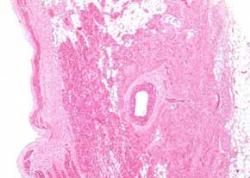

سلول‌هاي عضلاني قلب يا كارديوميوسيت‌ها موجب ضربان قلب مي‌شوند. دانشمندان مدتهاست كه براي توليد اين سلول‌ها از سلولهاي ديگر كه معمولا توليد سلولهاي بنيادي قلب و نخاع القا شده از ساير سلولها مانند سلولهاي پوست يا خون است، در حال تلاش هستند.